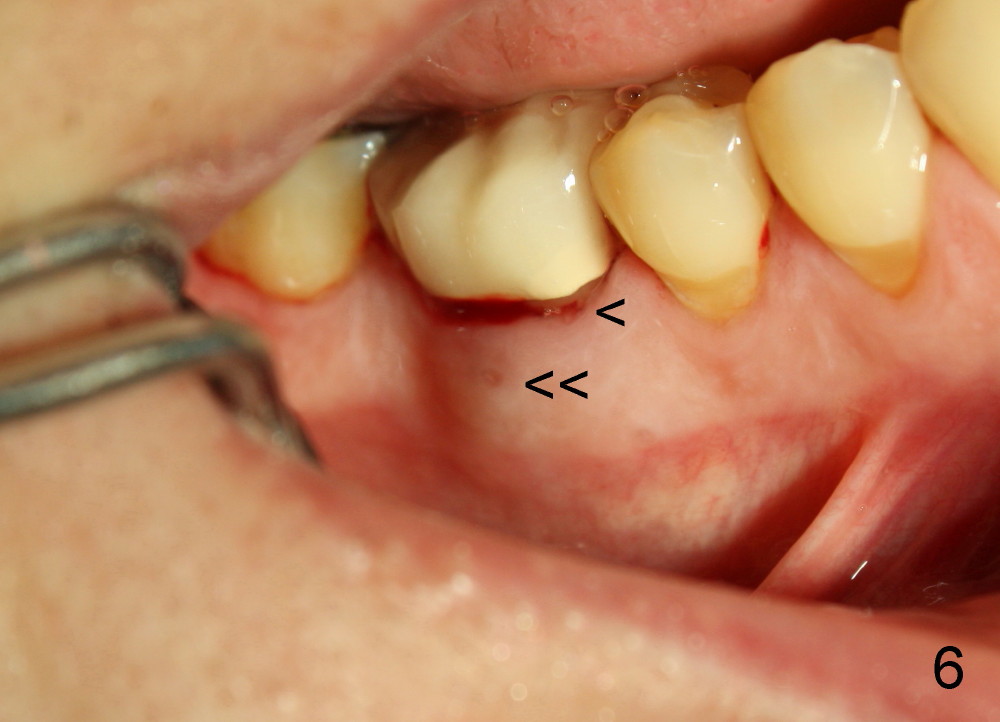

Dowman太太来自德国,收入不好,抽烟,不用牙线,结石多(图一箭头),右下第一磨牙远中龋齿(*)。她深洗还积极(图二已经没有明显结石),处理龋齿拖拖拉拉,九个月后,去龋时穿髓,暂封(图二*),她的后牙牙根特长,说明什么?下面回答。不得不做根管治疗(图三),图四是根管治疗后一年半拍摄,虽然根尖有阴影(箭头),但是病人没有任何症状。又过两年多病人主诉右下不适,根尖片显示根分叉阴影特大(图五*),近中根近中也有阴影(箭头),这时结石又出现。口内检查太容易了:右下第一磨牙颊侧有瘘道(图六双箭头),颊侧根分叉上皮附着失去(图六单箭头,也就是牙周袋深,探测出血),而舌侧根分叉牙周袋正常。总之,近中根有隐裂,接近颊侧,而远中根好像不容易出事,因为它比近中根粗。当我们为她牙齿惋惜时,老外比较爽快,说“It is not your fault. I love eating nuts. I grind my teeth at night. My night guard is too old to wear”。这段话可能说明为什么她后牙牙根长。